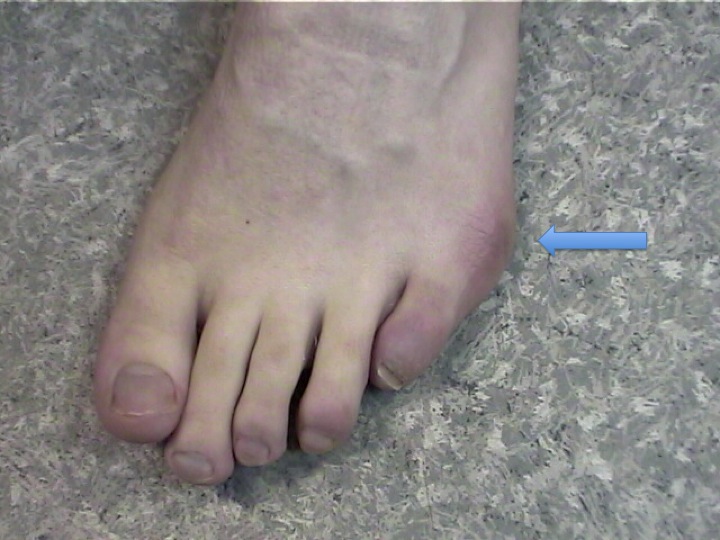

Se définit comme une instabilité et un conflit sur la cinquième tête métatarso-phalangienne et donc l’équivalent en miroir de l’hallux valgus, mais située sur le bord externe du pied.

Ils sont dus aux frottements et / ou la surcharge mécanique qui provoquent une inflammation ou des durillons sur le bord externe du cinquième métatarsien.

Cette malformation était typique chez les tailleurs, d’où son appellation, chez qui la position assise en tailleur créait une pression continue sur le bord externe du pied. La morphologie du cinquième rayon favorise le conflit lors du chaussage.